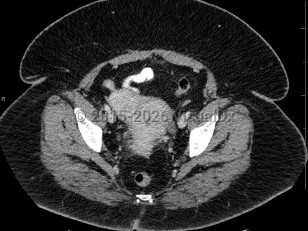

Imaging Studies image of Uterine fibroids - imageId=6844736. Click to open in gallery.  caption: '<span>Axial CT image demonstrates an exophytic fibroid arising from the uterus. </span>'

Axial CT image demonstrates an exophytic fibroid arising from the uterus.